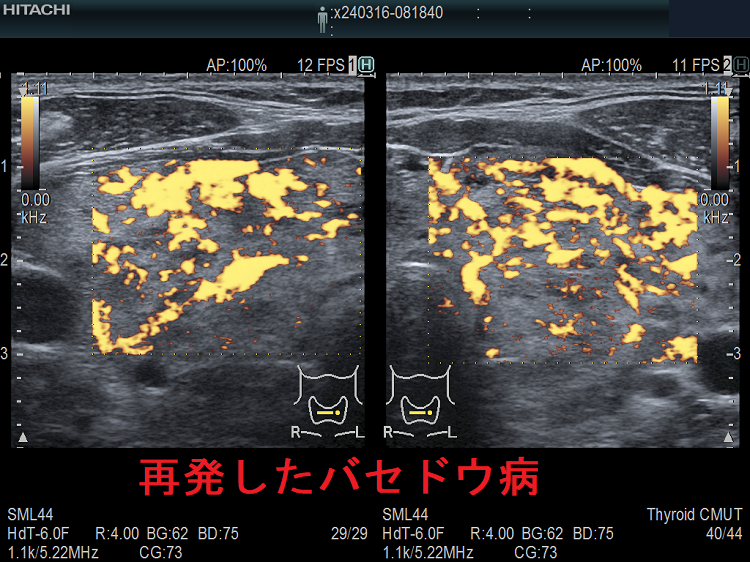

一般的な抗甲状腺薬の中止基準を用いてバセドウ病治療を中止後、再度甲状腺ホルモンが上昇して来たら、78%はバセドウ病の再発ですが、22%は一時的な甲状腺の破壊による無痛性甲状腺炎です(「上條甲状腺クリニックの甲状腺疾患Q&A」より)。

上條甲状腺クリニックの統計によると、バセドウ病/甲状腺機能亢進症の再発は、

- 1年以内再発62%

- 2年以内再発85%

- 3年以内再発92%

で、結局ほとんどが再発し、よくこんな中止基準を作ったものだと思います。

3年以上して再発しない人は、

- 平均11年そのまま寛解を維持

- 平均7年で3.3%再発

- 平均8年で3.7%甲状腺機能低下症に移行